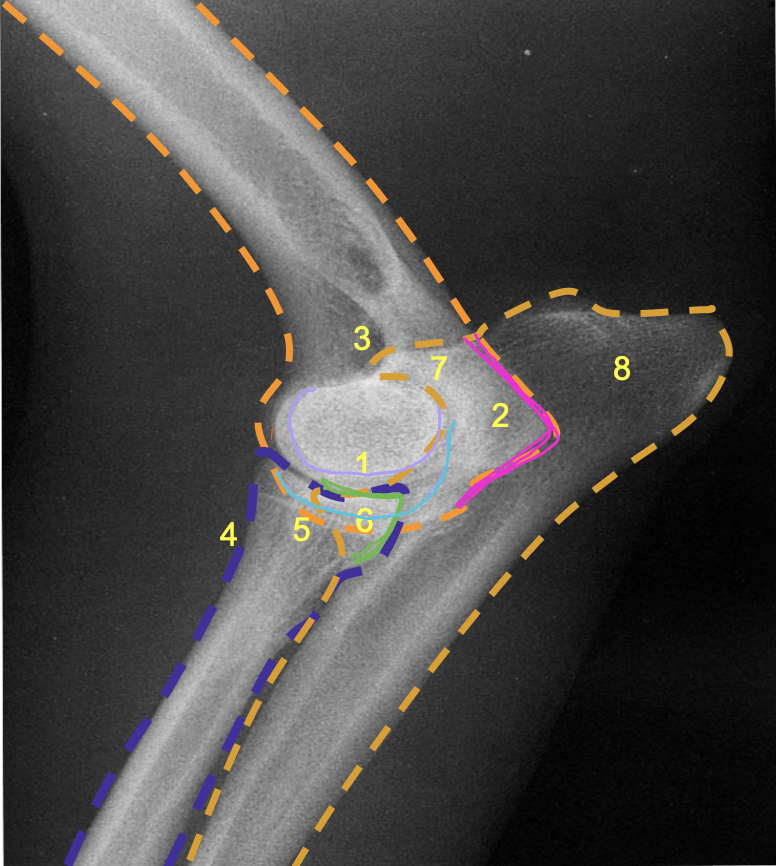

what is the pink line?

medial epicondyle of the humerus (makes 90 degree angle)

what is the purple line?

lateral condyle of humerus

what is the light blue line?

medial condyle of humerus

what is the green line?

medial coronoid process of the ulna

what is 8?

olecranon process of the ulna

what is 7?

olecranon of ulna

what is 1?

condyles of humerus

what is 2?

epicondyles of humerus

what is the red X marking?

anconeal process of the ulna